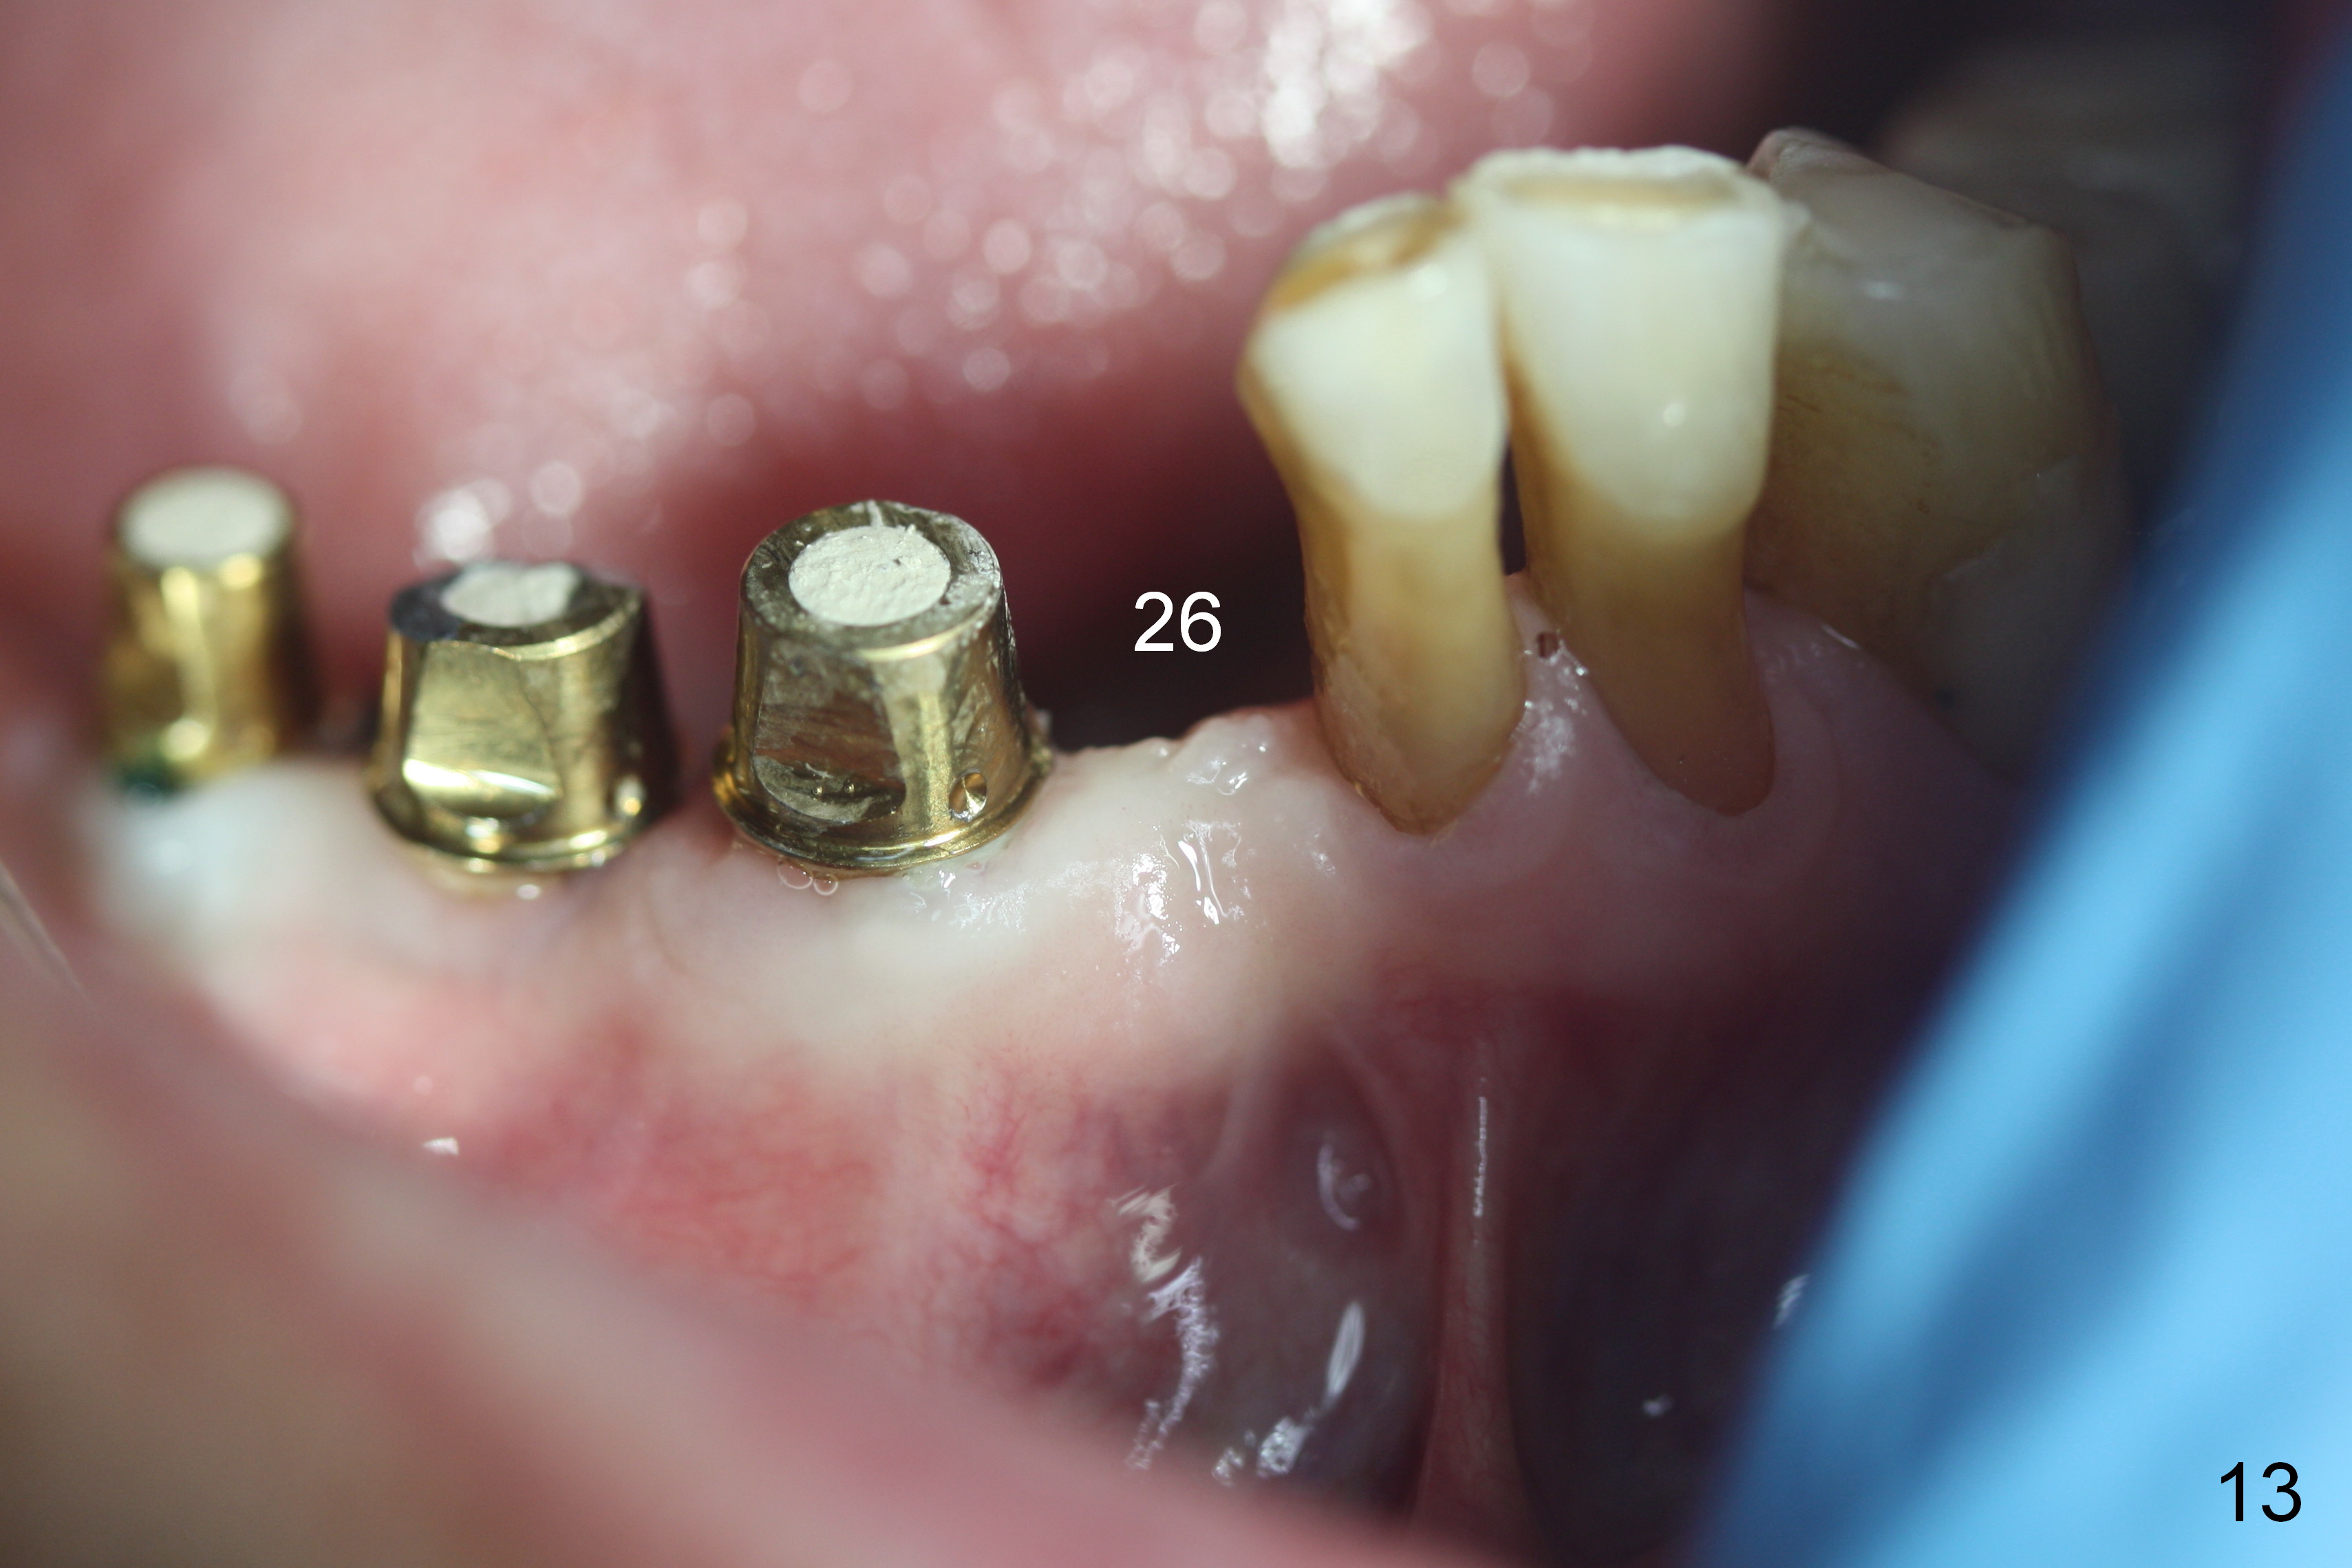

The patient returns for definitive restoration 5 months postop. There is no gross bone resorption around the implants (Fig.12). The surrounding gingiva is healthy (Fig.13). Since the edentulous space at #26 is relatively wide, one option is to splint #26-28 with #29 single. If the abutments at #27 and 28 are not parallel and the gingival margins are not at the same level too much, simply splint #26 and 27, since the implant at #27 is relatively long and wide.